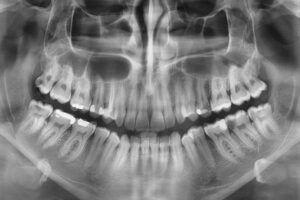

Denta Film, cabinet de radiologie dentară digitală, oferă soluții eficiente, într-un timp scurt, la un nivel minim de radiații. În cadrul acestui cabinet, pacienții pot beneficia de: radiografie digitală retroalveolară, radiografie digitală panoramică sau ortopantomografia, teleradiografie (cefalometrie), tomografie computerizată CBCT.

Cabinetul de radiologie Denta Film, situat în Cluj-Napoca, efectuează radiografii digitale 3D, radiografii cu imprimare laser de ultimă generație, oferind avantajul radiațiilor minime (cu 90% mai puţine radiatii decât în cazul unei radiografii clasice).

| Radiografia digitală panoramică (opt) | Tomografia Computerizată CBCT – CT 3D |